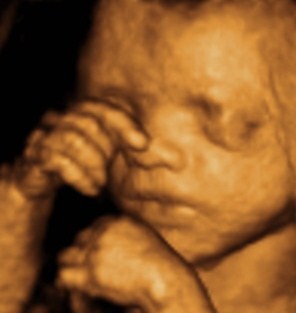

4D (FOUR-DIMENSIONAL), COLOR, DETAILED PREGNANCY ULTRASOUND

The photographic 3D (three-dimensional) image of a fetus was first made possible in the mid-90s with 4D (four-dimensional) Kretz technology. This technology added the factor of time to photographic images, making it possible to take videos in addition to the static photos we use today. This ultrasound examination, performed between the 18th and 23rd weeks of pregnancy, was previously known as ‘second-level’ or ‘color ultrasound.’ Today, doctors and patients mostly use the names ‘4D (four-dimensional)‘ and/or ‘Detailed Ultrasound.’ Regardless of which name is preferred, they all refer to the same examination, and the main goal is fetal anomaly screening.